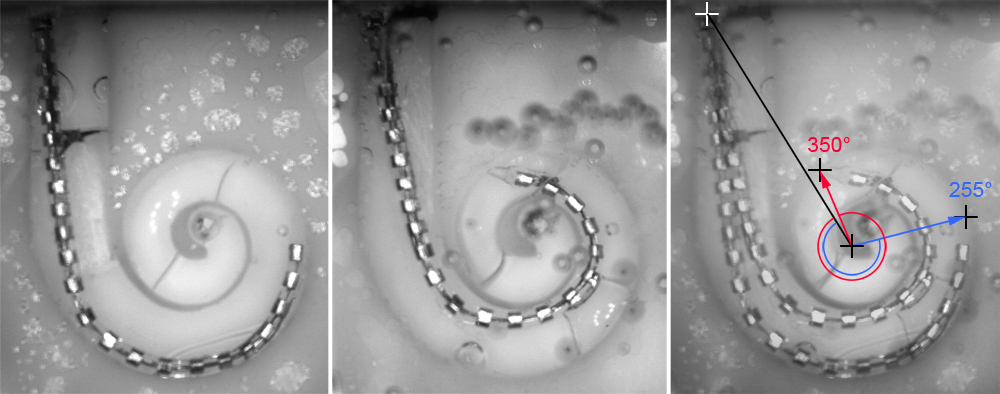

The situation is different when functionalizing the electrode carrier of a cochlear implant (CI) by use of Nitinol. The desired change of its shape from a straight configuration required for implantation towards a spiral shape (adapted to the cochlea) suggests the use of shape memory materials. However, an unsolved challenge is the concurrent preservation of the functionally important, membranous structures inside the inner ear. Consequently, the temperature-dependent actuation movement and the corresponding forces on the surrounding tissue have to be controllable and adjusted very accurately. In addition, the narrow surgical access causes a high heat input from the surrounding tissues, so that a precise timing of the temperature-dependent actuator is crucial. Thus, the cochlear implant serves as a prime example of a clinical application that requires both a very accurate adjustment of the thermo-mechanical behavior of the actuator to the clinical conditions as well as sufficient strategies to control the heat flow.

For several years, we have been exploring the shape memory effect of Nitinol, which is a well-established shape memory allow (SMA) made from nickel and titanium with numerous biomedical applications, as a potential mechanism for perimodiolar placement of the electrode array of a cochlear implant. A first demonstrator of this concept was announced in 2013 [Majdani et al.], referred to as Hybrid-M electrode array. Later we performed temporal bone studies to show that there ist no higher risk of insertion trauma due to the additional stiffness of the integrated Nitinol wire [Rau et al. 2016].

However, providing a functional EA for cochlear implantation surgery with shape memory effect is still an unsolved challenging issue due to the very narrow temperature range in which complete phase transformation has to take place. Fine tuning of the thermomechanical properties of the Nitinol wires requires further basic research in order to fulfil the application specific requirements.